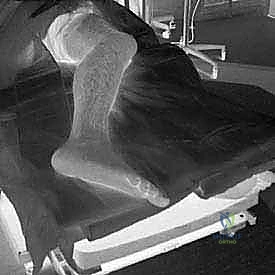

- التقييم السريري الشامل: فحص دقيق لمشية المريض، نطاق الحركة، نقاط الألم، فحص قوة الأوتار، والتأكد من سلامة التروية الدموية والأعصاب.

- الأشعة السينية (X-rays) متعددة الزوايا: لتقييم الانهيار العظمي وزوايا الكعب (مثل زاوية بوهلر وزاوية جيسان).